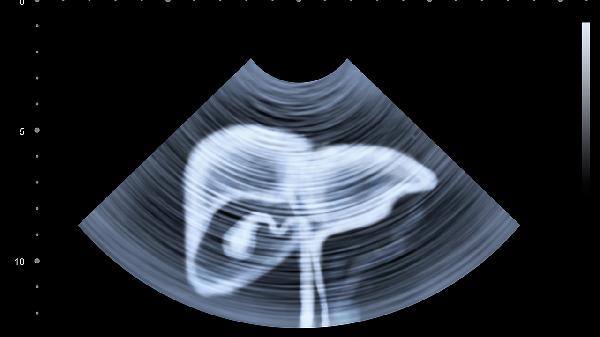

四、膈面定位

肝臟膈面緊貼膈肌,最高點(diǎn)位于右側(cè)第五肋間鎖骨中線位置。呼吸運(yùn)動(dòng)時(shí)肝臟隨膈肌上下移動(dòng)約2-3厘米,這種動(dòng)態(tài)變化在超聲檢查中尤為明顯。膈面肝臟與右肺底僅隔薄層膈肌,在胸部創(chuàng)傷時(shí)易受累。